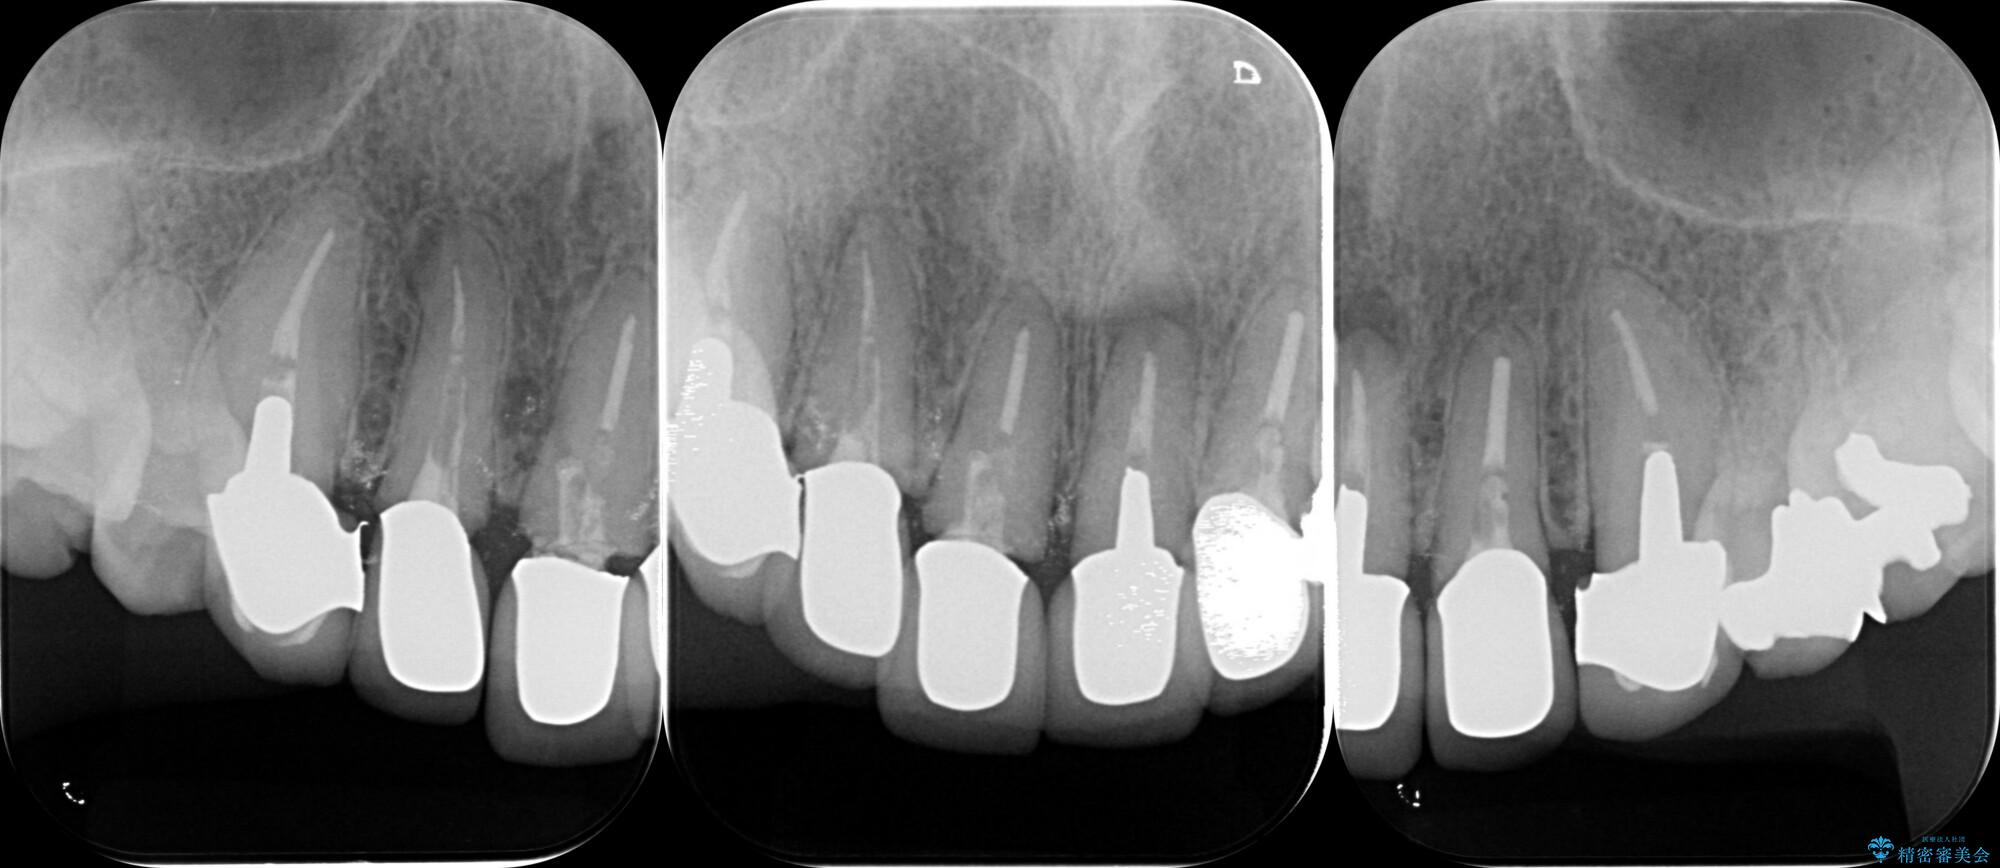

装着されていたセラミックを除去したところ、歯ぐきの奥深くまで歯牙は削られ、歯ぐきの炎症・出血が著しくみられる状態でした。

この状態で再度セラミッククラウンの作製・装着を行ってもまた同じ状態となってしまうため、歯周外科を行い歯ぐきの状態を整備したのちセラミッククラウン治療をおこなっていきます。